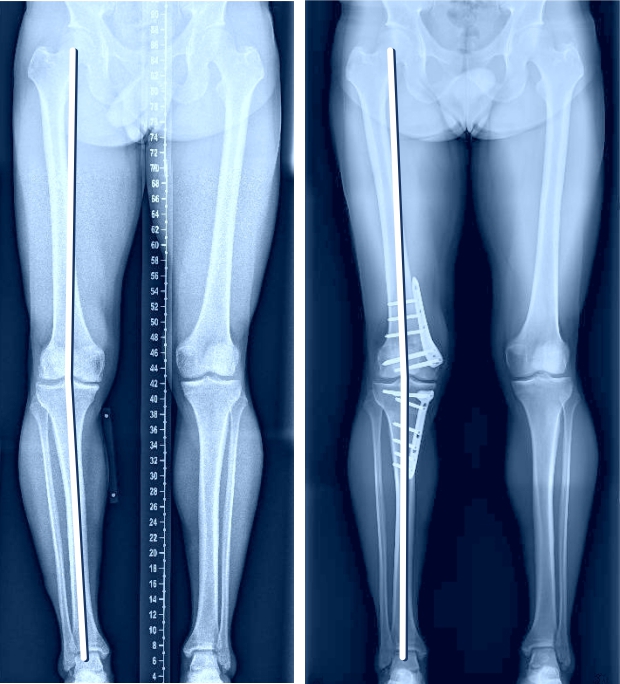

Wenn nur auf der Innen- oder der Aussenseite des Kniegelenks eine Arthrose vorliegt, kann mit einer sogenannten Umstellungsosteotomie oft eine Linderung der Beschwerden über Jahre erzielt werden, ohne dass ein künstliches Gelenk eingebaut werden muss. Wenn nur die Innenseite des Kniegelenks von der Arthrose betroffen ist (O-Beine), während die äussere Gelenkhälfte völlig schmerzfrei ist, kann mittels Umstellungsosteotomie durch eine Knochendurchtrennung im oberen Schienbeinbereich ein leichtes X-Bein erzielt werden (sogenannte Valgisationsosteotomie), was zur Entlastung der inneren Gelenkhälfte führt. Ziel ist es, unter Erhalt des eigenen Gelenks die Schmerzen zu vermindern und das Fortschreiten der Arthrose aufzuhalten oder zumindest zu verzögern. Zur Behandlung der Valgusgonarthrose (X-Fehlstellung) erfolgen Knochendurchtrennung und Achsenkorrektur knienah meistens am Oberschenkel (Varisationsosteotomie). Ist die Fehlstellung sehr ausgeprägt ist es manchmal sogar notwendig, in derselben Operation am Ober- und Unterschenkel einen Korrektureingriff vorzunehmen.

Beispiel einer sogenannten Doppel-Osteotomie, bei der sowohl am Oberschenkel als auch am Unterschenkel eine Korrektur gemacht wurde, zur korrekten Ausrichtung der Beinachse und Gelenkslinie.